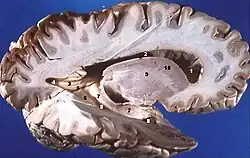

Grey matter is distributed at the surface of the cerebral hemispheres (cerebral cortex) and of the cerebellum (cerebellar cortex), as well as in the depths of the cerebrum (the thalamus; hypothalamus; subthalamus, basal ganglia – putamen, globus pallidus and nucleus accumbens; as well as the septal nuclei), cerebellum (deep cerebellar nuclei – the dentate nuclei, globose nucleus, emboliform nucleus, and fastigial nucleus), and brainstem (the substantia nigra, red nucleus, olivary nuclei, and cranial nerve nuclei).

Additional images

- Human brain right dissected lateral view